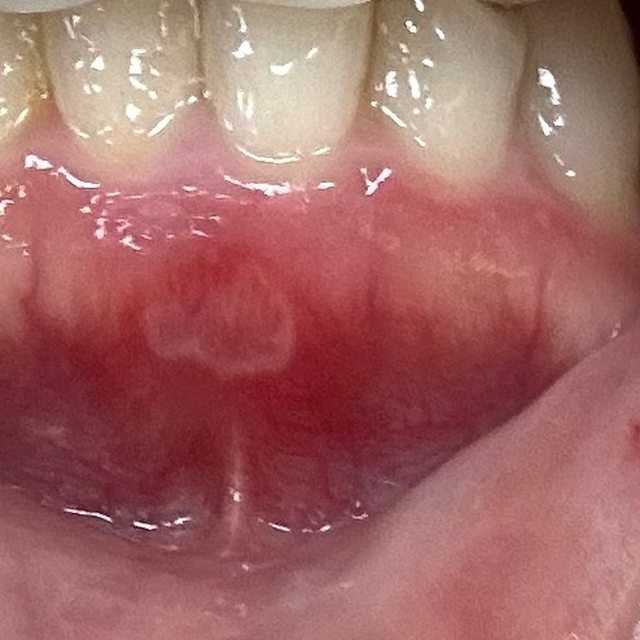

這個酷東西是之前我新冠肺炎的時候,嘴破+喉嚨痛,我朋友推薦我買的噴劑,但她推的 是得伏寧的,那時沒買到買了上圖的。 他那個噴頭可以伸很深去噴喉嚨痛。也可以去噴破洞,我通常是真的很痛,擦完藥會再噴 一下這個,就會麻麻的。這單噴的止痛效果不大,最好跟其他主攻產品一起使用。 實戰演練! 先來張嘴破圖: . . . . 防雷 . . . . . . . https://i.imgur.com/dK5XQGH.jpeg

破在下排牙齦處,這前期還好,不要看它沒有很白,它後期長大根本大魔王。它很會選位 置,這位置基本上不管做什麼事(吃飯、喝水、講話)都一定會碰到,我那個禮拜真的很 想死 它小時候我是用妥治安+口內膏。一般的痘痘有可能就消失了,但它很不一般,持續長大 ,等他長到圖上那麼大,真的太痛,我真的沒勇氣繼續使用妥治安。 我期間也有使用大正貼片,原本用紅色版本(二類醫藥品)但是它黏性和止痛效果沒有粉 紅色好,加上它破的位置會一直被嘴唇拉扯到,貼片半掉不掉無限拉我的傷口,很生氣! ! 後來改用粉紅色,只後悔怎沒早點用!!只要一貼上去,我的嘴巴就是一片淨土。 但因為它一直消失不了,最後加上每天吃B2這魔王才給我消失的。 它消失之後我還是繼續吃B2,這次月經來的時候,又有小洞準備要破,但它的痛程度整個 比魔王輕很多,幾乎連藥也不太需要認真擦,它就自己消失,很沒存在感。 一不小心打太多,認真分享給所有嘴破的戰友們。如果有其他更強的方式拜託分享一下! -- ※ 發信站: 批踢踢實業坊(pttweb.org.tw), 來自: 220.138.216.253 (臺灣) ※ 文章網址: https://pttweb.org.tw/WomenTalk/M.1717999901.A.42A